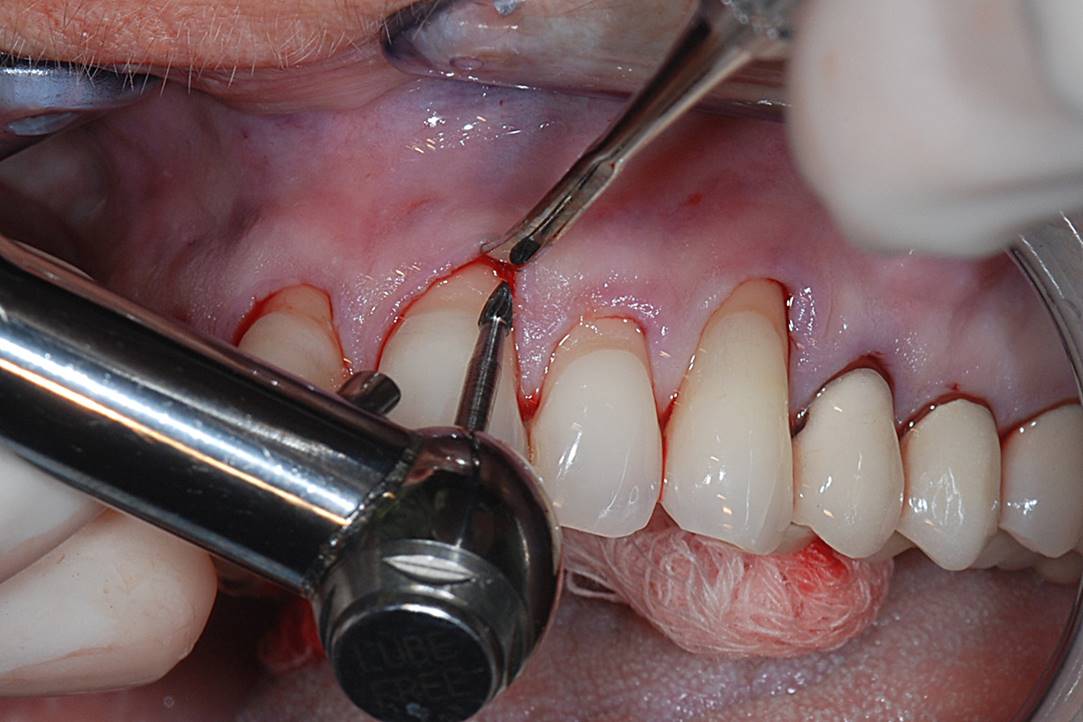

A patient presented with moderate recession requiring root coverage and increased thickness of the alveolar housing (Figure 9). A series of parallel incisions was completed using instruments made specifically for microsurgery; these incisions were performed utilizing high magnification (ie, 5.5 magnification via loupes). The distance between the incisions was roughly the amount of root coverage necessary on the adjacent teeth (Figure 10).25

The isthmus of tissue between the parallel incisions was removed. A split-thickness flap was elevated leaving connective tissue on the bone and providing access for root preparation.

To ensure a smooth root surface, rotary instruments with finishing burs and curettes are used. A glycine air-polishing unit (eg, Air-Flow Master, Hu-Friedy, hu-friedy.com) was used to impart the final smoothing of the roots and remove the smear layer and biofilm.

The CTG was then harvested from the palate as previously described and placed over the roots (Figure 11). The primary flap was advanced to cover the graft; a dual blood supply was assured from the underlying tissue and the overlying flap. Atraumatic suturing was performed using fine sutures (eg, Resorba® 6-0/7-0 Resolon™, Osteogenics Biomedical, osteogenics.com) to approximate the flap margins.